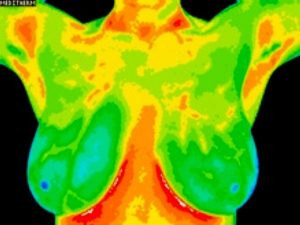

Breast Thermography

Breast thermography is a simple, pain-free, and safe way to monitor your breast health. There is absolutely no touching, no radiation, and no breast compression! All women’s breast, half, and full body scans are performed by a female certified clinical thermographer.

Breast thermography screens for indications of:

- Cysts

- Lymphatic congestion

- Hormonal imbalances

- Generalized inflammation

- Fibrocystic breasts

- Inflammatory breast disease

- Tumors of the breast

- Angiogenesis